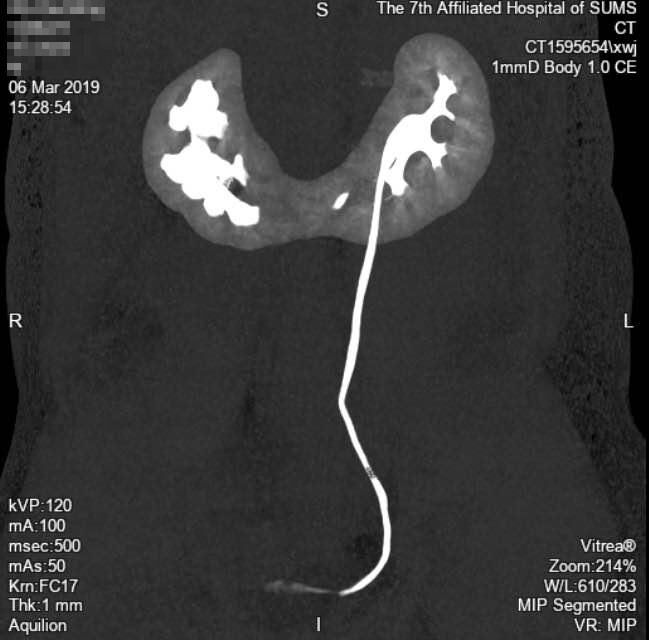

入院后完善检查发现,马先生右肾多发结石范围达到了 5.39cm。而且,他的两肾还很奇特,是非常罕见的 “马蹄肾”。

马蹄肾是一种肾融合畸形,指两侧肾脏在中线通过肾实质或纤维组织形成的峡部相连,相连的部位多为下极。通俗来讲就是明明是一左一右两个肾,如今成了一对 “连体肾”。

“马蹄肾在人群中的发病率约为 0.25%,男女之比约为 2:1。可以说是千里挑一。”泌尿外科主任庞俊说,马先生 CTU 检查右侧输尿管未显影,说明结石已引起梗阻,若梗阻引起积水逐渐加重,则会损害肾功能,严重时导致肾无功能。

经过详细讨论,庞俊决定通过微创的方法取出结石,这样对病人的身体伤害最小,利于恢复。与正常人的肾脏相比,马蹄肾的位置比较深,并伴旋转畸形,所以穿刺比较困难,但是,在泌尿外科医护人员的精心准备下,最终在 X 光引导下顺利穿刺至肾盂,采用单通道钬激光碎石的方法将马先生的结石完整去除,手术过程十分顺利。目前,马先生已出院,各方面指征显示身体恢复良好。